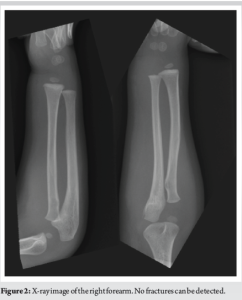

A 2-year-old boy was taken by his parents to the emergency department of our hospital 3 hours after falling from a chair. He had no family history of congenital hemorrhagic diseases nor anticoagulant medications. In his physical evaluation, he was crying and was found to be in right extremity pain with diffuse swelling and firming of the forearm. His right distal forearm to hand was congested with a clear border to the proximal forearm (Fig. 1), although the right radial pulse was palpable. He resisted attempting passive finger movement due to pain. It could not confirm his active finger movement, assess his sensory disturbance of the hand because his verbal ability was immature, nor detect any fractures in the X-rays of his right wrist, forearm, and elbow (Fig. 2). We found that the physical evaluations satisfied only two of the five P sign, which were pain and paralysis. Still, we diagnosed him with AFCS without fracture and immediately decided to perform a fasciotomy. According to his laboratory data, the platelet count was within the standard limit. However, neither bleeding time, prothrombin time, activated partial thromboplastin time, nor international normalized ratio was examined. Neither computed tomography (CT), magnetic resonance imaging (MRI), Doppler ultrasonography, nor angiography was performed, as the shortening of time to surgery was chosen over the findings obtained from these tests. The intra-compartmental pressure of his right forearm was elevated over 80 mmHg under general anesthesia before surgery. Carpal tunnel release and extensile fasciotomy were performed in the dorsal, superficial volar, and deep volar compartments of his right forearm. A hematoma was found in the carpal tunnel of the distal forearm, and curettage was performed between the superficial and deep volar compartments (Fig. 3). Neither the radial nor ulnar arteries were occluded or blew actively. None of the vascular tumors around the carpal tunnel, vascular malformation of the arteries, or necrosis of the forearm muscles was observed. Following carpal tunnel release and fasciotomy, the tension of each compartment of the forearm was relieved, and the congestion of the hand improved immediately. Since primary closure was not possible due to soft-tissue swelling, the shoelace technique was used initially. Postoperatively, intravenous cefazolin sodium, 0.4 g every 12 h, was given for 48 h to prevent surgical site infection. For pain management, intravenous acetaminophen was given as needed. No occupational therapy was started during the postoperative period. On the 23rd postoperative day, an attempt was made to achieve partial primary closure. However, during suturing, high tension made it challenging to palpate the radial artery, potentially blocking blood flow. Consequently, the remaining areas were covered with split-thickness skin grafts. After surgery, to prevent scarring at the incision site, tension reduction with tape and topical application of heparinoid were continued for 6 months afterward. Two years after surgery, he had no signs of motor and sensory neurological defects in his right upper extremity. Given that he was only 4 years old, evaluating his upper limb function was not possible by patient-reported measures such as the Quick-Disabilities of the Arms, Shoulders and Hands. He also had a barely noticeable matured wound scar without hypertrophic scarring or skin contracture (Fig. 4). Moreover, he has never experienced episodes indicating potential hemorrhagic tendency or vascular disorders.